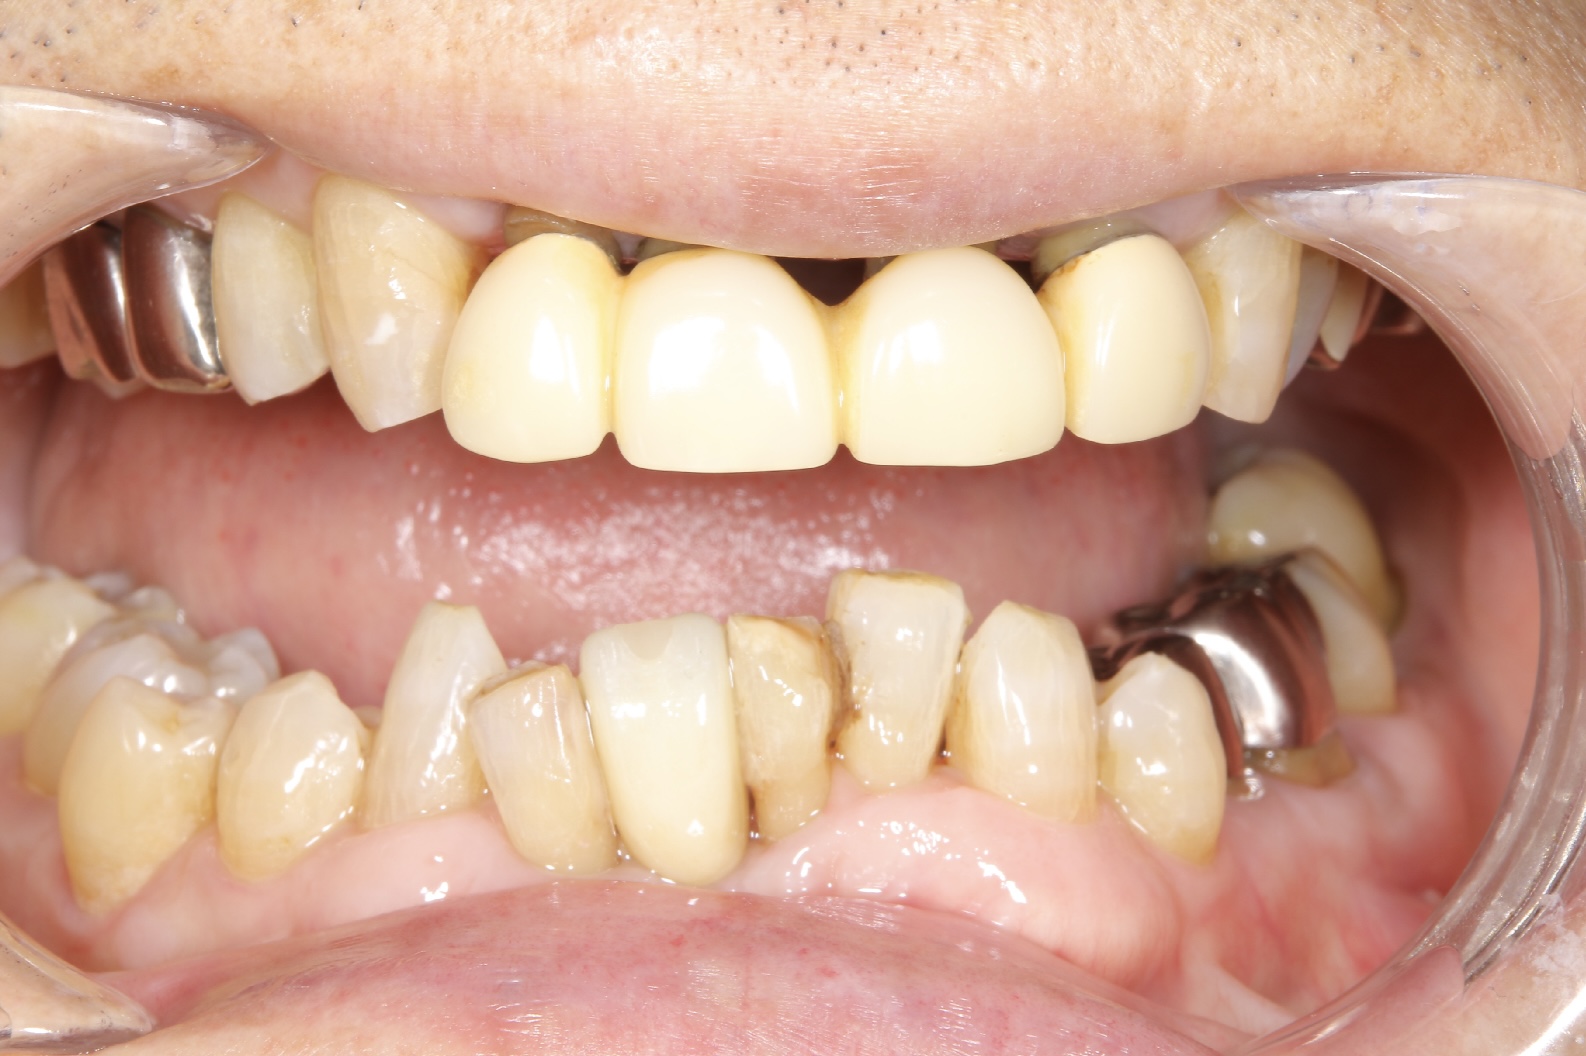

世界でも数多くの歯科医師に選ばれている「ストローマンインプラント」を採用。先進設備による精密な検査・診断と丁寧な処置で、埋入手術による痛みや腫れを減らし、安定性の高い長持ちするインプラント治療を提供しています。